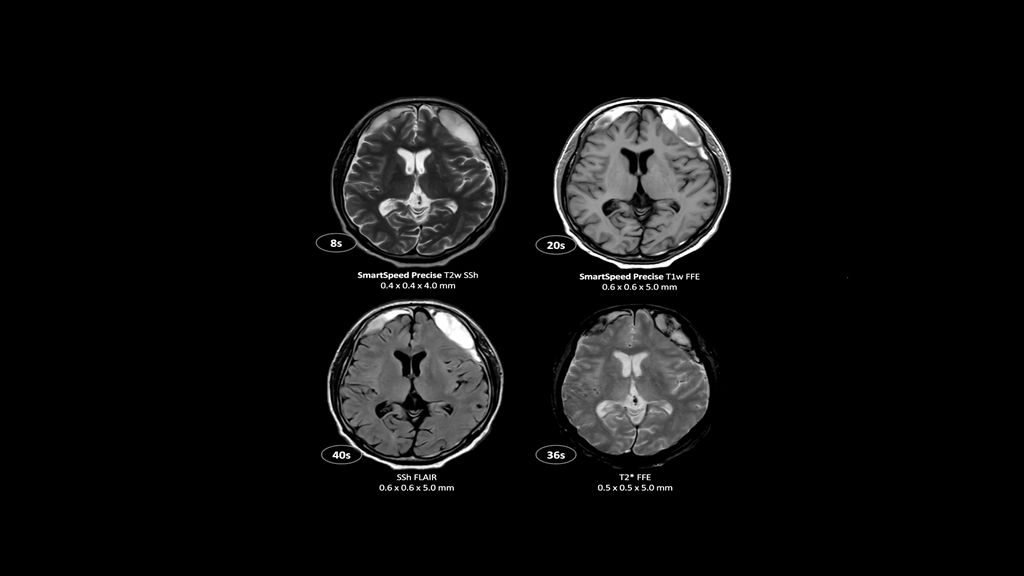

2. Reconstruction technology Compared to conventional (SENSE/ Compressed SENSE, SmartSpeed AI) imaging. Sharpness was evaluated with phantom scanning.